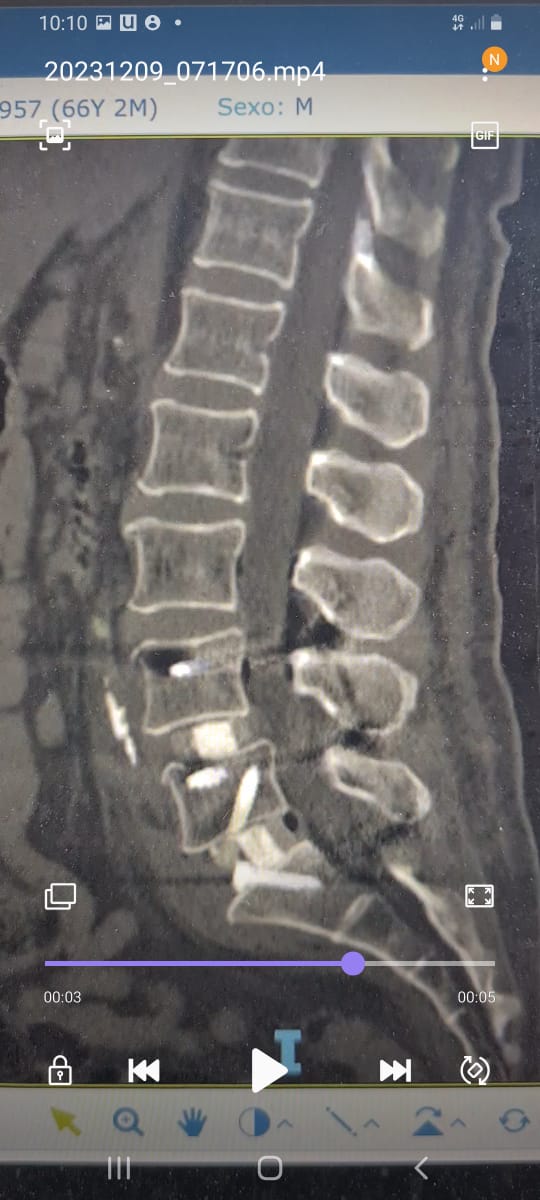

“Fueron tres tipos de exposiciones. Una de ellas es la cirugía en vivo, donde realizamos dos procedimientos en pabellón, acompañados por destacados especialistas, el Dr. Carlos Zanardi, presidente de la Sociedad de Neurocirugía de Buenos Aires, Argentina y el Dr. Cristiano Meneses, director del Instituto de Columna de Brasil”, precisó el Dr. Muñoz.

A continuación, compartimos las fotografías enviadas por el Dr. Avaria a la Sociedad de Neurocirugía de Chile: